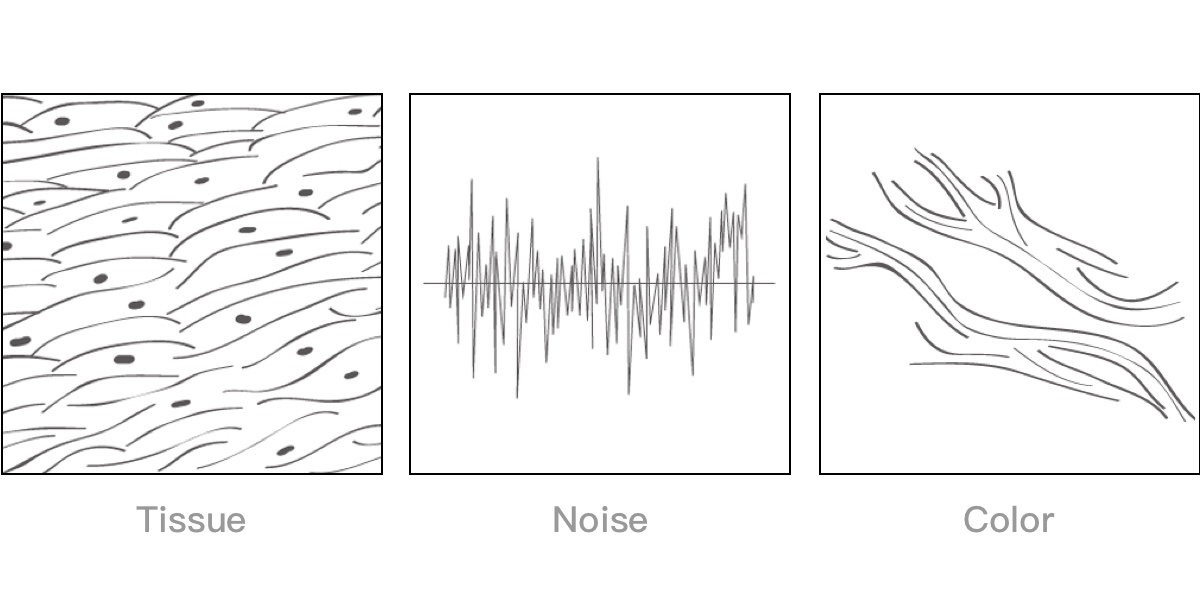

通过对组织运动信息、血流信号及背景噪声进行准确智能的阈值判定,高效提取出微弱血流信号,获得高灵敏度和空间分辨率的血流图像,为临床提供更加真实和丰富的诊断信息。